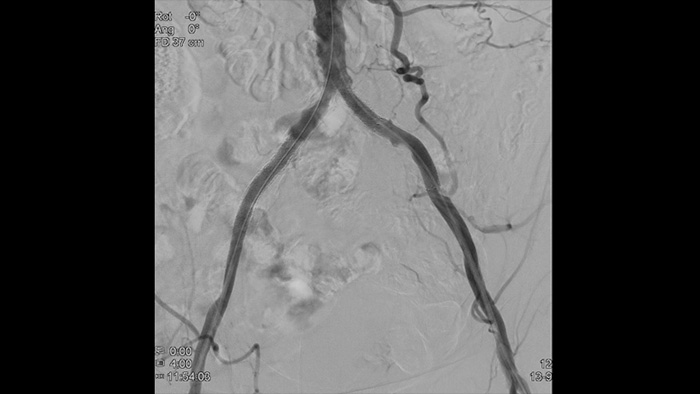

Изображения высокого разрешения позволяют детально рассмотреть сосуды, и таким образом обеспечивают точное проведение лечения, навигации и последующего наблюдения за пациентом.

Четкая визуализации. Оптимальная тактика лечения Решения Philips позволяют врачам получать больше информации, чем может предоставить ангиограмма, способствуя тем самым выбору оптимального лечения.